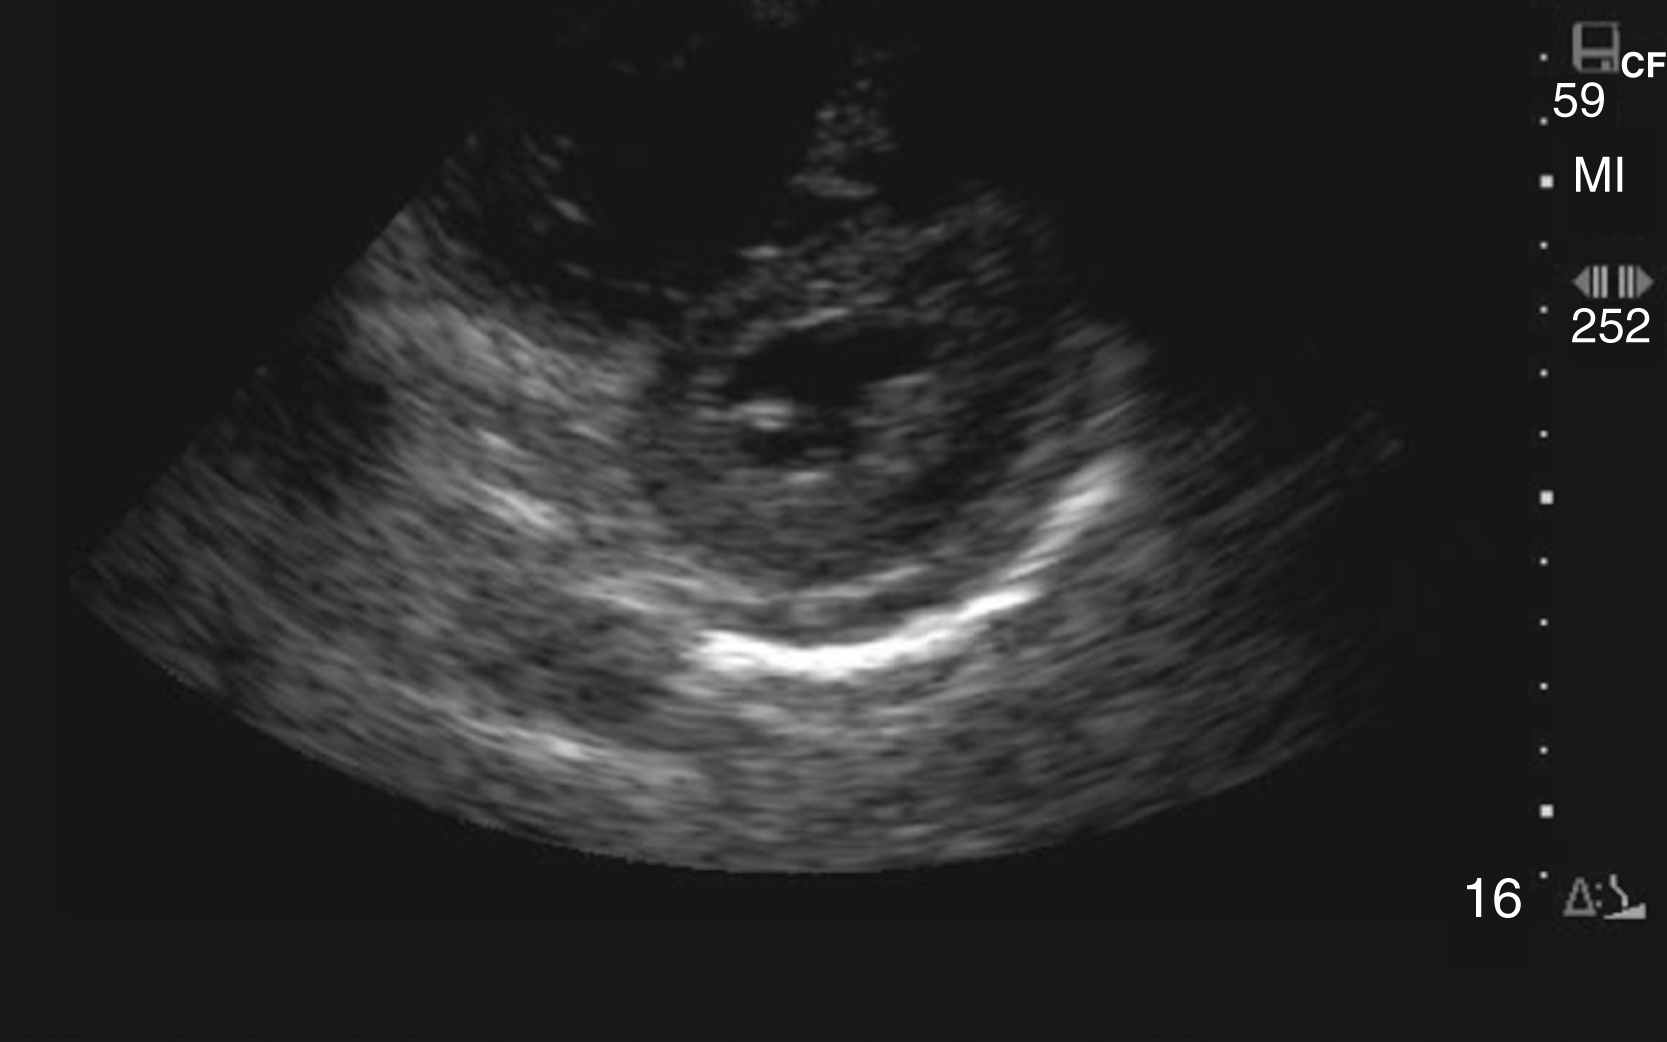

Image Acquisition

Cardiac US is performed through the transthoracic and transabdominal windows with the use of small curvilinear or phased array transducers. Typical views include the subcostal four-chamber view (subxiphoid), parasternal long-axis view ( Fig. e3.10 ; see Video e3.4 ), parasternal short-axis view, and apical four-chamber view. The subcostal four-chamber view, as in the FAST, is ideal for assessment of pericardial effusion and useful during cardiac arrest because it does not interfere with chest compressions. The long-axis subcostal view highlights the inferior vena cava (IVC) and can indicate volume status. The parasternal views are excellent windows for LV assessment. The apical four-chamber view is ideal for comparison of RV and LV sizes and function. Several US protocols have been developed to evaluate undifferentiated hypotension and can be used to narrow the differential diagnosis.

Normal parasternal long-axis view of the heart.